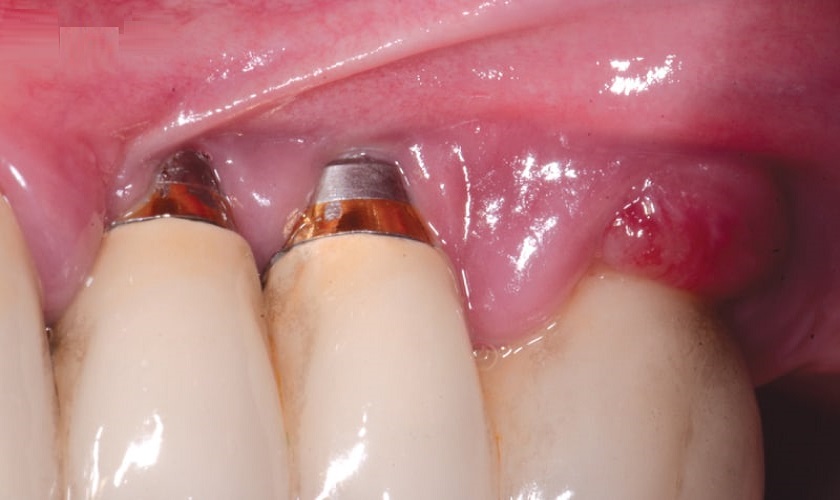

Lộ trụ Implant – Nguyên nhân, hậu quả và cách điều trị

Lộ trụ Implant sau khi cấy ghép răng có thể xảy ra do xương hàm không đủ số lượng, thể tích cho việc tích hợp, đặt trụ Implant không chínhXem thêm